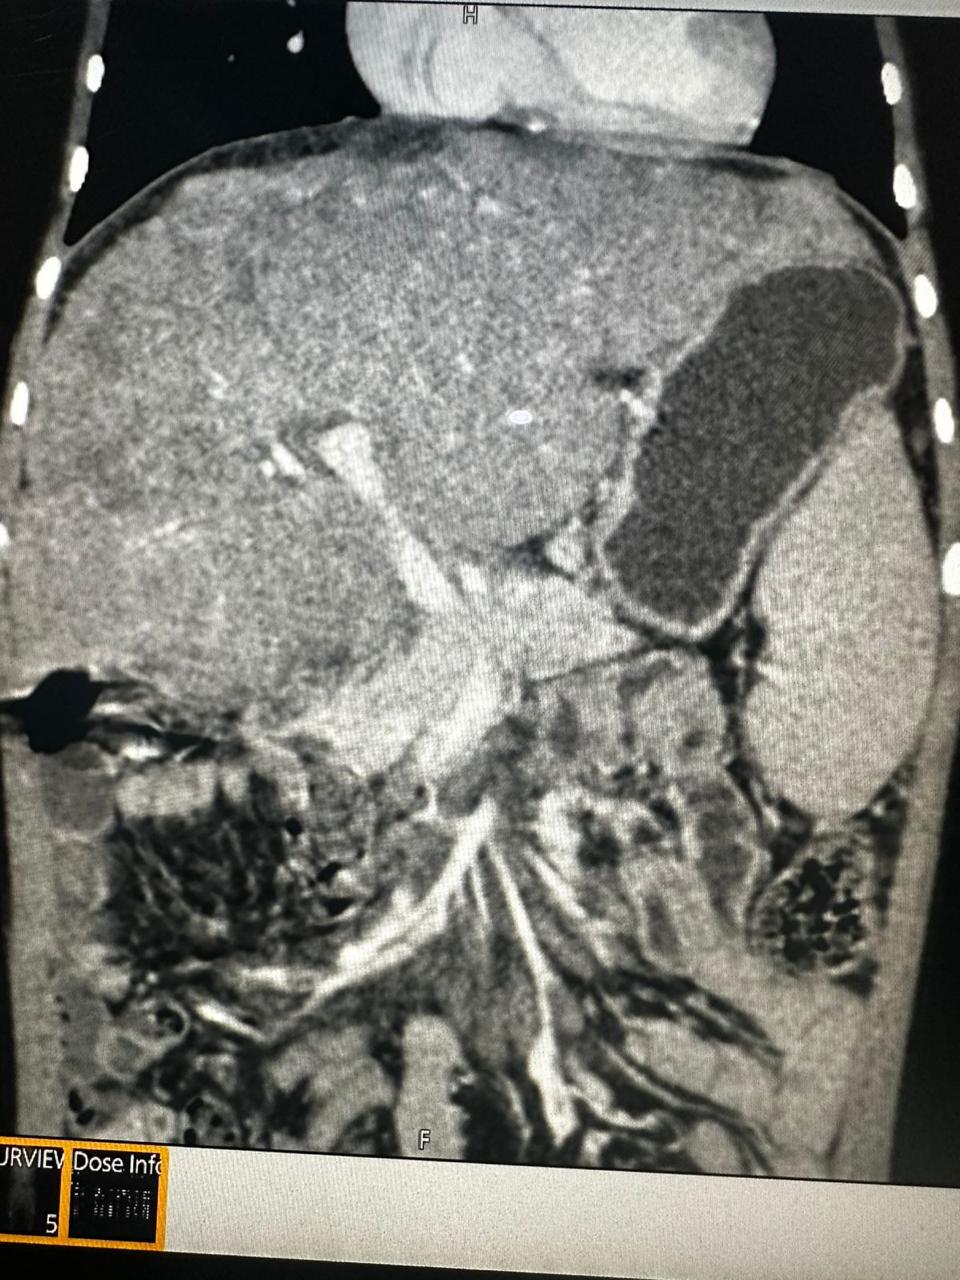

Peripheral Angioplasty procedure at Sarda Vascular Centre Dehradun

Interventional Radiology (IR) uses real-time imaging such as X-ray, ultrasound, CT, or MRI to guide tiny instruments through the body for treatment — without large surgical incisions.